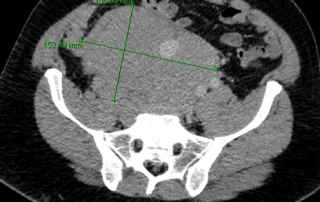

Classement rémission complète avec adénomégalies résiduelles sous- diaphragmatiques non hypermétaboliques

Décision : R-CHOP21 x 8 cycles avec prophylaxie neuro-méningée par 4 PL méthotrexate, en raison de l’IPIaa à 2 et des LDH augmentée. Evaluation par scanner après 4 cycles et par TEP-FDG après 8 cycles.

Classement LNH diffus à grandes cellules B CD20+, stade III, OMS = 1, LDH augmentées soit 2 facteurs selon IPIaa.

Biopsie d’une adénopathie sus-claviculaire conduit au diagnostic de lymphome diffus à grandes cellules B CD20+, CD5-, CD10-, BCL6+, BCL2 faible. Biopsie médullaire normale.

Gastroscopie et écho-endoscopie digestive : estomac normal. Adénopathies coeliaques confluentes, pancréas normal.

Biologie hémogramme hémoglobine 10,8 g/dl, LDH 180% la valeur normale. Bilan hépatique normal.